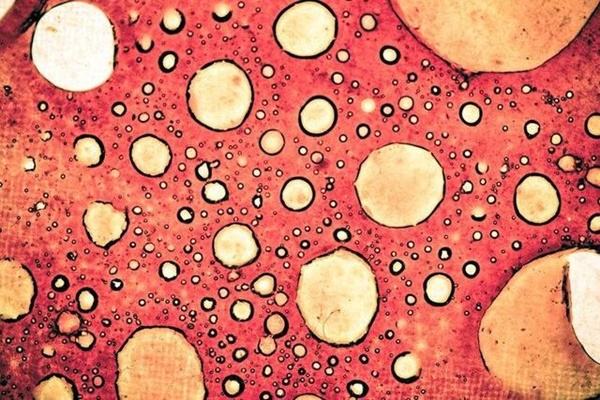

Ung thư là một khối u được hình thành do sự tăng sinh bất thường hoặc đột biến của các tế bào dưới tác động của nhiều yếu tố, cả yếu tố chủ quan và yếu tố khách quan từ môi trường. Một khi ung thư hình thành, nó sẽ dần nhân lên ở một mức độ nhất định, sau đó xâm nhập, phá hủy các mô xung quanh và thậm chí xảy ra di căn toàn thân, từ đó dẫn đến suy giảm hoặc làm mất chức năng của các cơ quan trong cơ thể. Cuối cùng bệnh nhân sẽ tử vong do suy cơ quan hoặc suy toàn thân.

Các tế bào này phát triển cục bộ không giới hạn trong cơ thể, hình thành sự tăng sinh bất thường và trở thành tổn thương tiền ung thư. Lúc này, tế bào ung thư chưa phá vỡ màng cơ bản giữa tế bào và mô nên sẽ không di căn, và chúng sẽ bị đào thải ra khỏi cơ thể nếu hệ miễn dịch đủ mạnh.